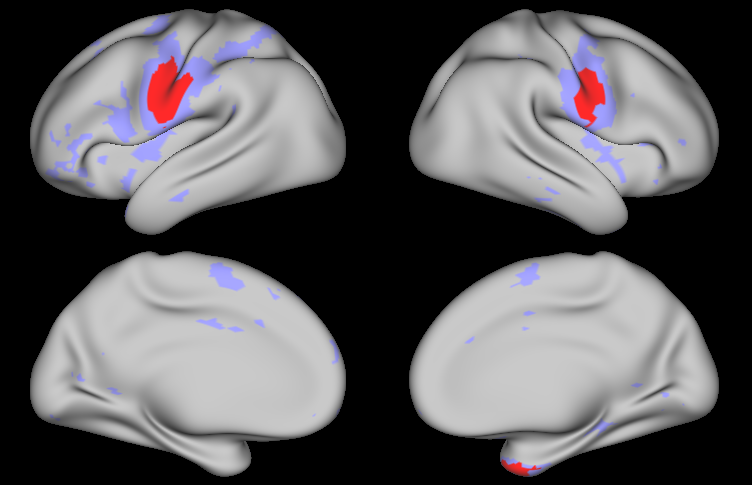

Figure LABEL:fig:app99 shows the regions of activation identified by thresholding the joint PPM excursion function for each task, along with those identified through the classical GLM with FDR and FWER correction, using significance level 0.010.010.01 in each method. For the Bayesian GLM, regions of activation at activation threshold γ=0𝛾0\gamma=0 are shown in purple, while those at γ=0.027𝛾0.027\gamma=0.027, corresponding to 1%percent11\% of the global baseline signal, are shown in red. Several effects are clearly notable. First, the areas of activation based on controlling the FWER in the classical GLM are very conservative. This is a well-known issue with this approach that worsens as the number of locations increases, which is likely why FWER correction produces reasonable results in the simulation study but very conservative results on real fMRI data. FDR control results in significantly larger areas of activation, reflecting an increase in power while maintaining a known degree of false positive control. Second, the areas of activation based on γ=0𝛾0\gamma=0 in the Bayesian GLM are similar to those based on FDR control in the classical GLM, but are smoother and somewhat larger. This likely reflects an increase in power resulting from incorporating spatial dependencies in the Bayesian GLM, as observed in our simulation study. Third, compared with the joint model, the areas of activation based on the Bayesian two-level model are smoother but similar in size. This illustrates that while the two-level approach tends to result in somewhat oversmoothed estimates, the sampling method described in Section 3.1 is able to appropriately account for uncertainty in the subject-level estimates when fitting the group-level model. Finally, the increased power in the joint PPM results in widespread areas of activation based on γ=0𝛾0\gamma=0, while the more biologically meaningful threshold of γ=0.027𝛾0.027\gamma=0.027 (1%percent11\% of the baseline signal) results in more conservative areas of activation that correspond well to the highly activated areas shown in yellow in Figure LABEL:fig:app:beta.